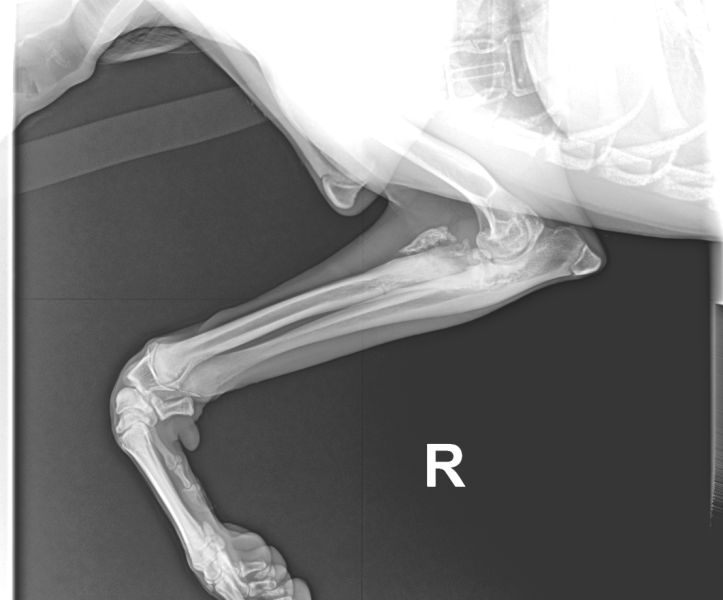

Der größte Schock allerdings für u n s, war ein Tierarztbesuch am Montag. Sonny`s rechter

Ellbogen war wesentlich dicker als sein Linker. Klar, wir röntgen, denn evtl. Interssenten sollen

wissen, was Sache ist. Die Röntgenbilder waren eine Katastrophe!!! Das Ellbogengelenk war nicht

mehr intakt, ein Knochenteil schwebt frei in neu gebildetem Kallus. Und diese Verletzung war a l t!

Bei einem 7 Monate alten Hund! Den Rest des Tages erlebte ich in einer Schockstarre. Aus Irland

Die Röntgenbilder

sind mittlerweile in mehreren Kliniken mit erfahrenen Knochenspezialisten. Wir werden hoffentlich

einen Weg finden, dieses Gelenk wieder herzustellen, bzw. Sonny überhaupt ein Leben bieten zu

können.